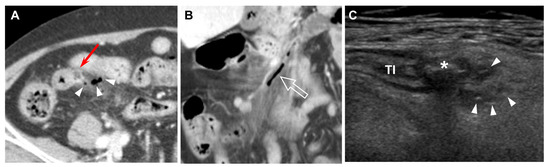

Figure 1. Forty-eight-year-old female (patient #8) with acute ileal diverticulitis. (A) Coronal reformatted enhanced CT scan reveals an outpouching diverticular sac (red arrow) connecting to the terminal ileum and mild ileal wall thickening. (B) US scan with C8-5 convex transducer demonstrates a homogeneous hypoechoic diverticular sac (*) connecting to the terminal ileum (TI), surrounding hyperechoic inflamed fat (arrowheads), and mild wall thickening of terminal ileum (TI). (C) Color Doppler imaging shows increased color flow to the diverticular wall and surrounding inflamed fat.

The CT findings for acute ileal diverticulitis are summarized in Table 2. All 17 patients had ileal diverticulum along the mesenteric border. Inflamed diverticulum was seen in 16 patients (94.1%) (Figure 1). The remaining patient did not have an inflamed diverticulum at the center of ileal wall thickening with abscess; however, adjacent ileal diverticula supported the diagnosis of acute ileal diverticulitis with perforation, and barium study after 1 month demonstrated two ileal diverticula along the mesenteric border (Figure 2). Three patients had radiodense fecalith within the inflamed diverticulum (Figure 3). All 17 patients had mesenteric fat infiltration with varying degrees and ileal wall thickening. Five patients (29.4%) were diagnosed with perforated ileal diverticulitis, which had the following findings: abscess (n = 2) (Figure 2), extraluminal fluid with air (n = 3) (Figure 4), and/or focal defect in the diverticular sac (n = 2) (Figure 5). Mesenteric venous gas (Figure 4) and mesenteric venous thrombosis were seen in two patients (11.8%), respectively.

The US findings for acute ileal diverticulitis are summarized in Table 3. All patients showed outpouching inflamed diverticular sac connecting to the ileum, peridiverticular inflamed fat presenting as hyperechoic fat around the diverticulum, and increased color flow to the diverticulum and surrounding inflamed fat on CDI (Figure 1). The inflamed diverticulum exhibited variable echogenicity (Figure 2 and Figure 3). Like CT findings, eight patients had a single diverticulum and nine patients had multiple diverticula. Unlike CT, US examinations diagnosed perforated ileal diverticulitis in seven patients. The findings indicated that five patients had both abscess and extraluminal air bubble (Figure 4 and Figure 5), one patient had only extraluminal air bubble (Figure 6), and one patient had only abscess.